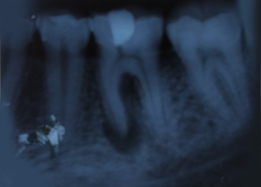

Radiograph with Prosthesis (8 Months)